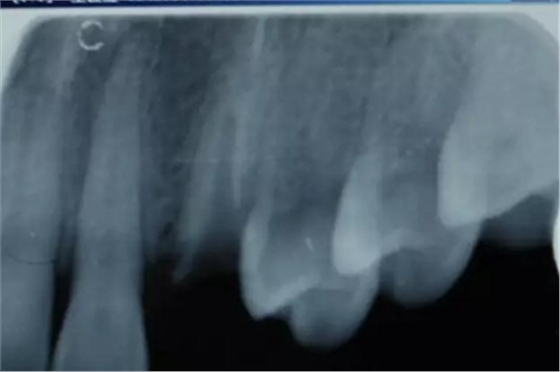

患者女性,55歲,3年前B3纖維樁+鑄瓷全冠修復(fù),一周前牙冠折斷,就診后,發(fā)現(xiàn)纖維樁根管口處折斷,周圍牙齦增生,建議患者行冠延長手術(shù)。首先去除斷端的纖維樁。拍片示牙根長度充足。于是開始冠延長手術(shù)。

因為是前牙,故該患者將來修復(fù)體邊緣必須為齦下,所以3個月后再行修復(fù)。以下為手術(shù)前照片。